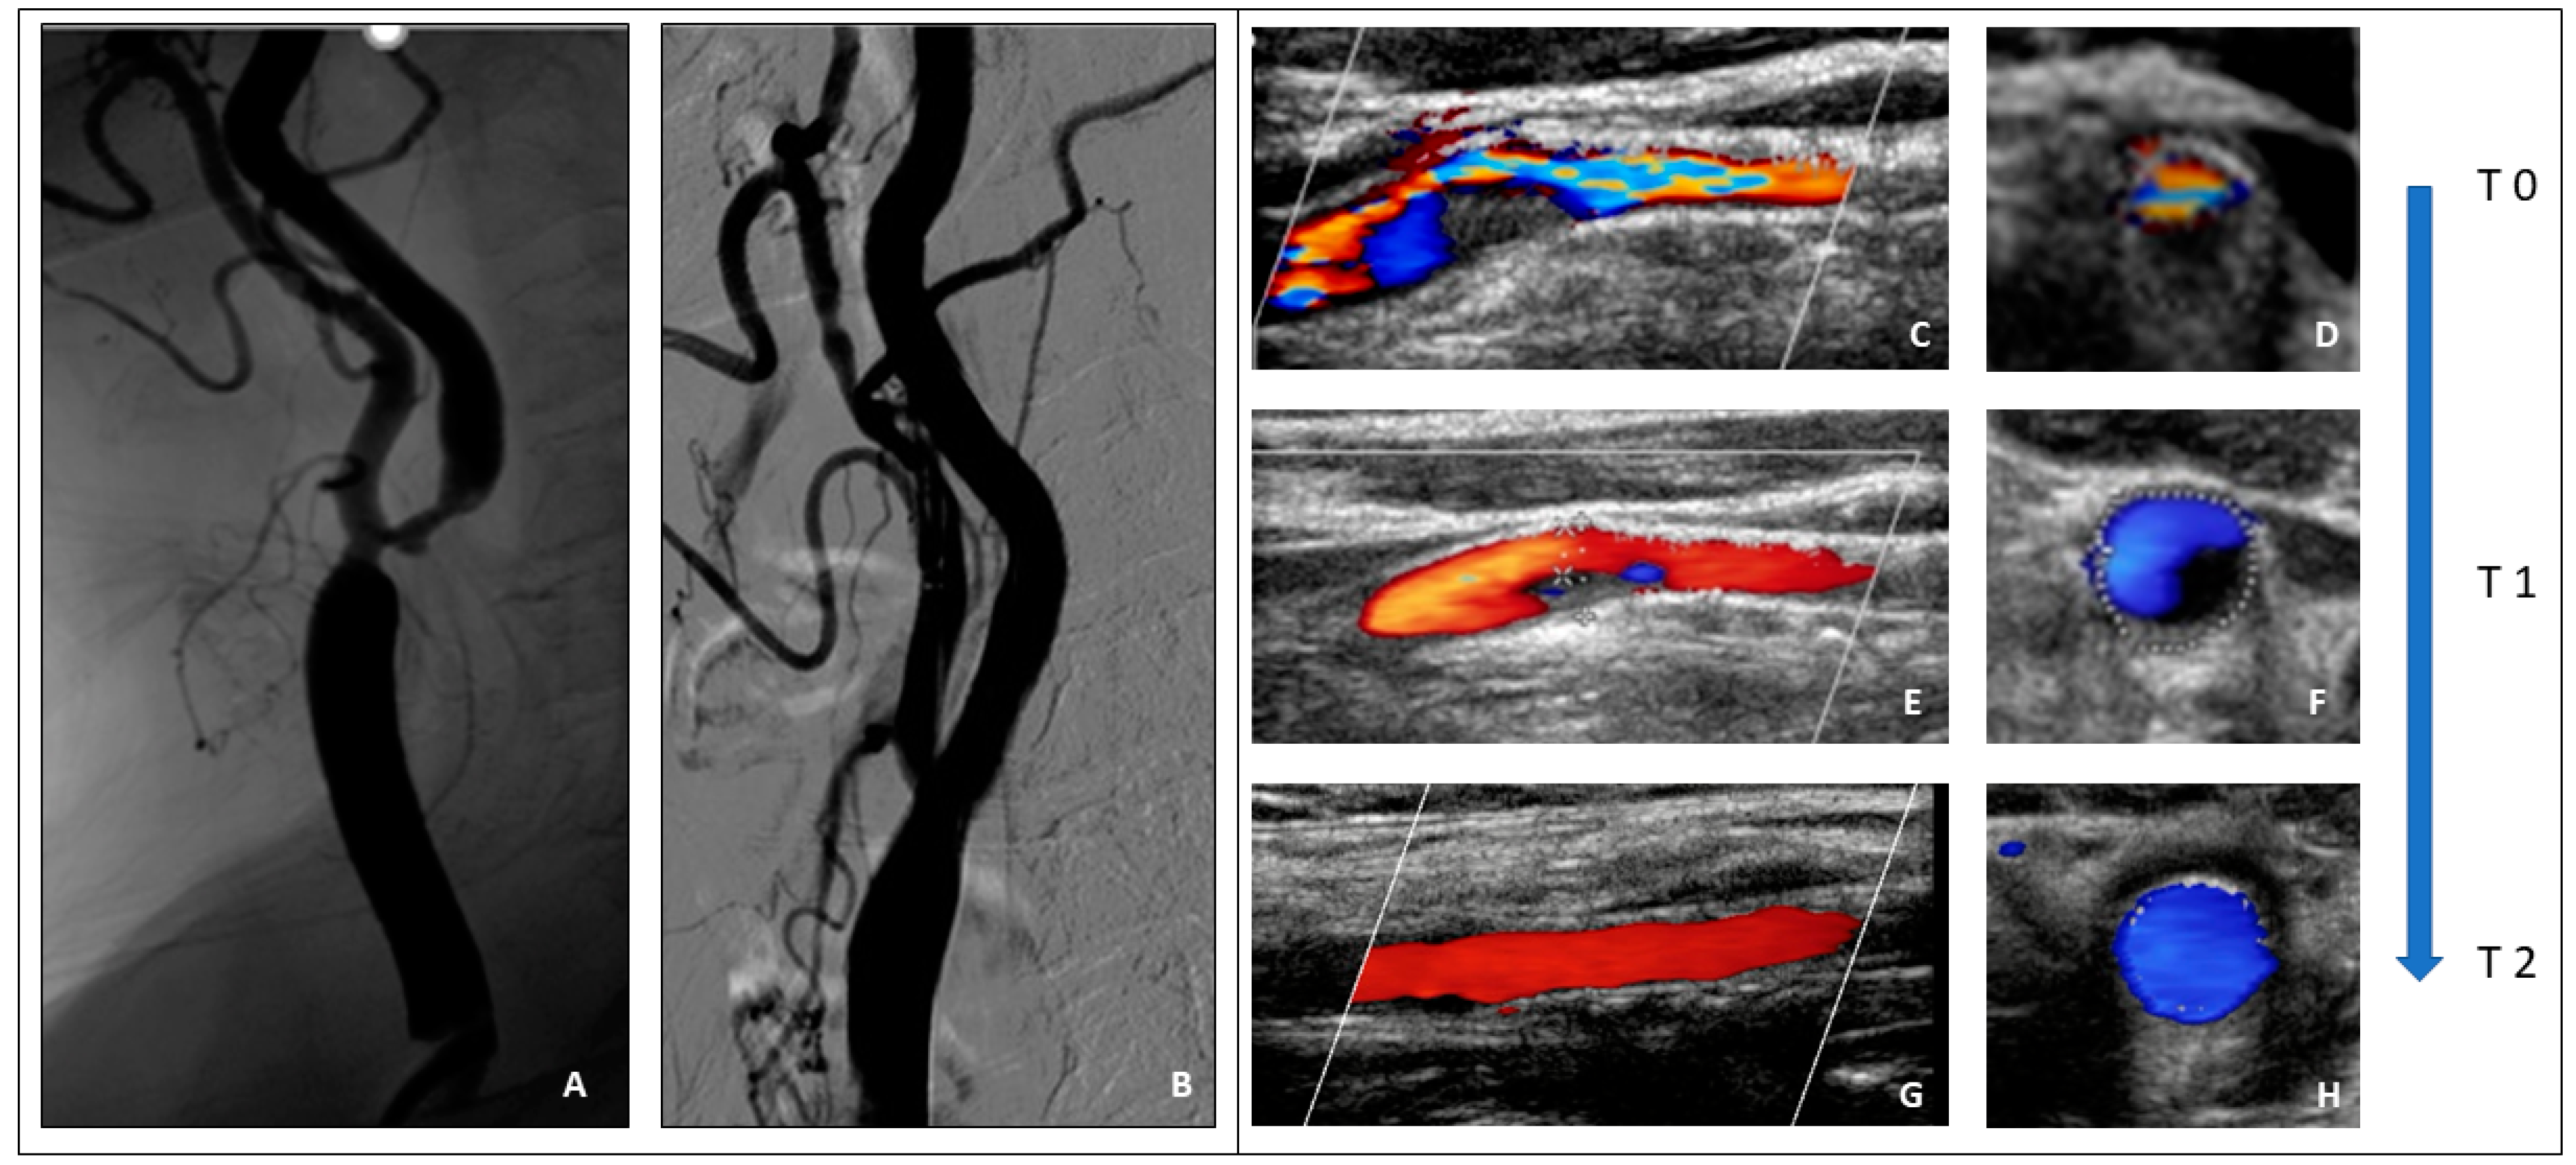

- Cerebral hyperperfusion syndrome (CHS)

- Brief case description